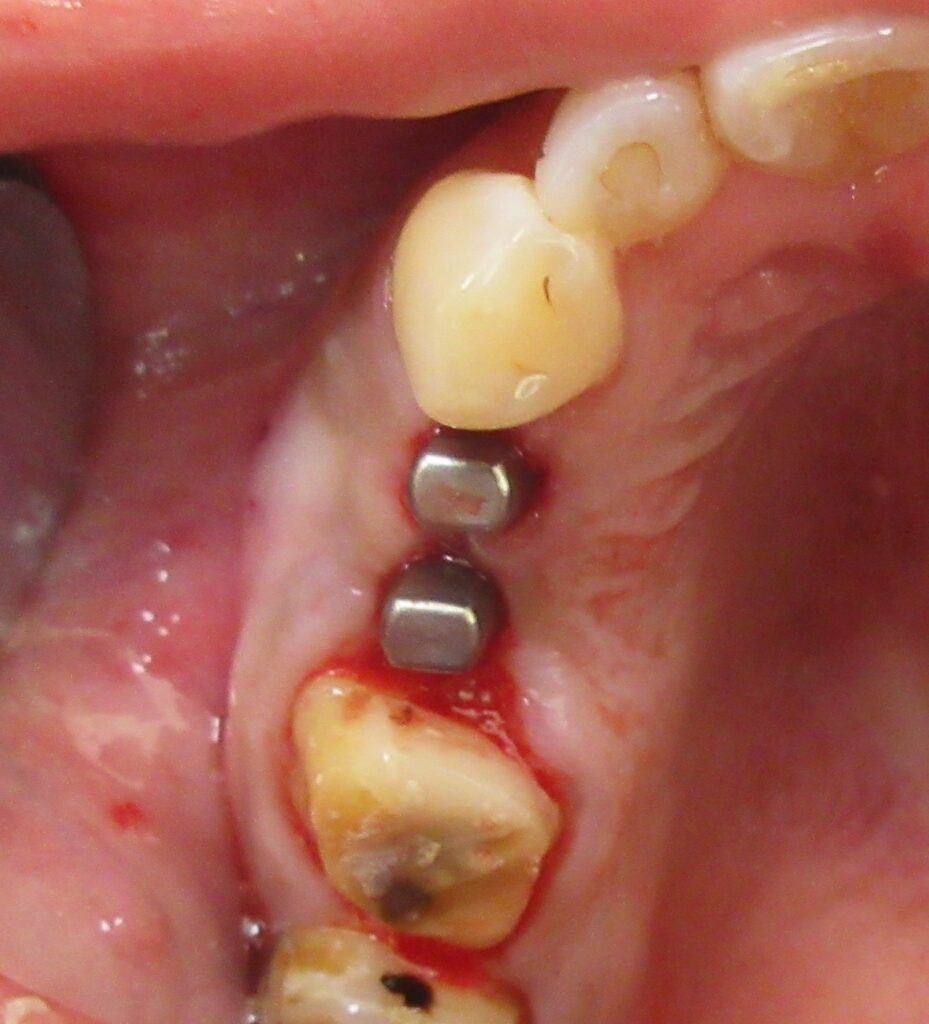

開けた穴に、専用道具を使ってネジを締めるように長さ2センチ程のインプラントを骨に埋め込んでいきます。

続けて他の歯も同じように植立していきます。

インプラントオペでは、複数本を植立する場合でも、当時進行はせず、1本ずつ同じ工程を繰り返して植立します。